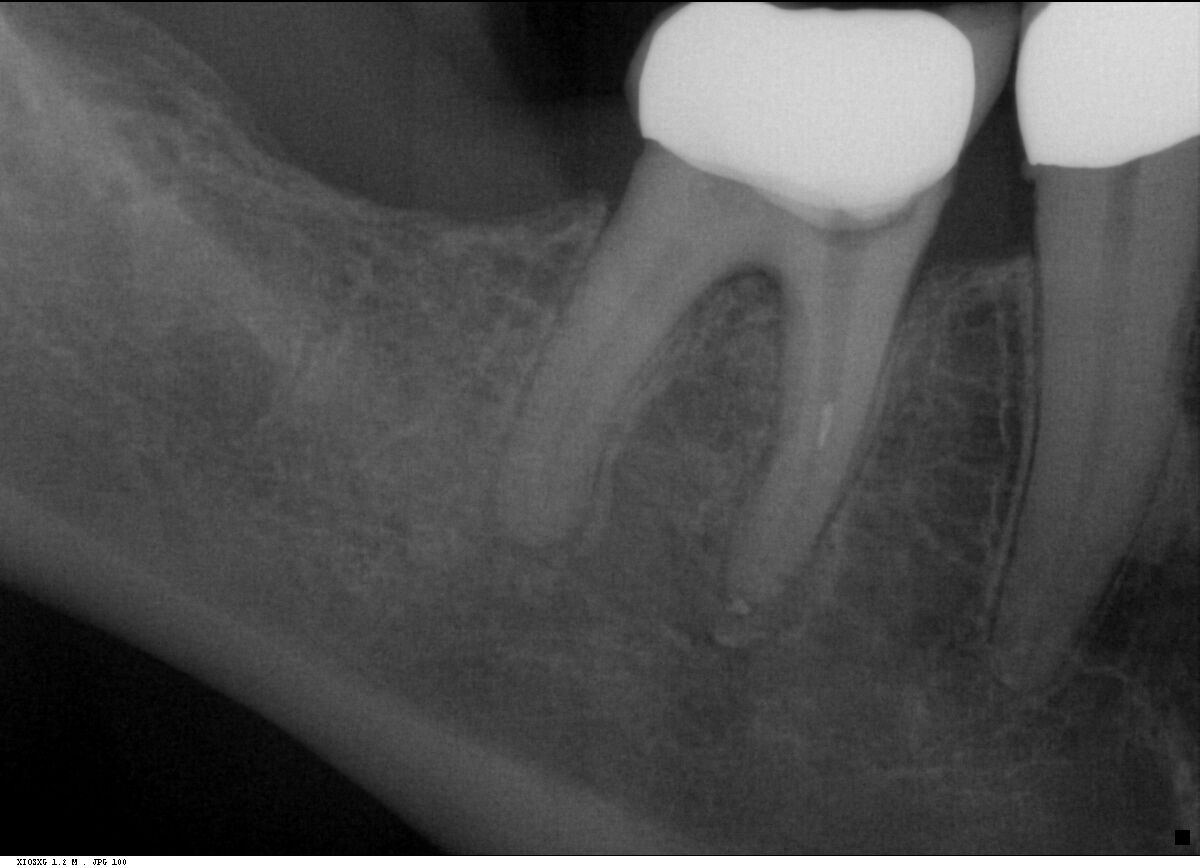

Fall 4: großer interradikulärer Entzündungsherd

Endodontie Fall 4: großer interradikulärer Entzündungsherd

Vor der Behandlung